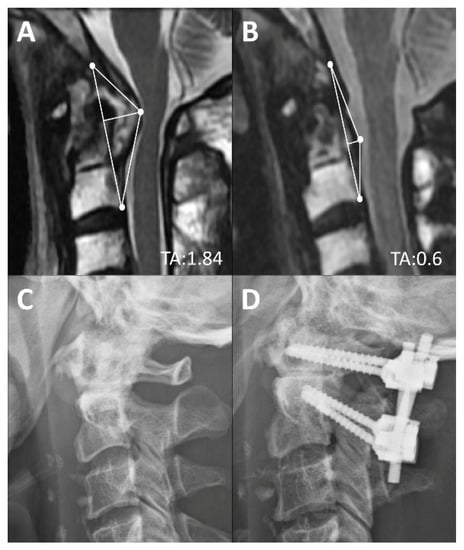

| Surgery (n = 81) | 1.67 ± 0.51 | 1.34 ± 0.47 † | 1.21 ± 0.37 † |

| Complete Reduction (n = 47) | 1.52 ± 0.44 | 1.12 ± 0.39 † | 1.03 ± 0.39 † |

| Partial Reduction (n = 34) | 1.81 ± 0.52 | 1.59 ± 0.46 † | 1.41 ± 0.2 † |